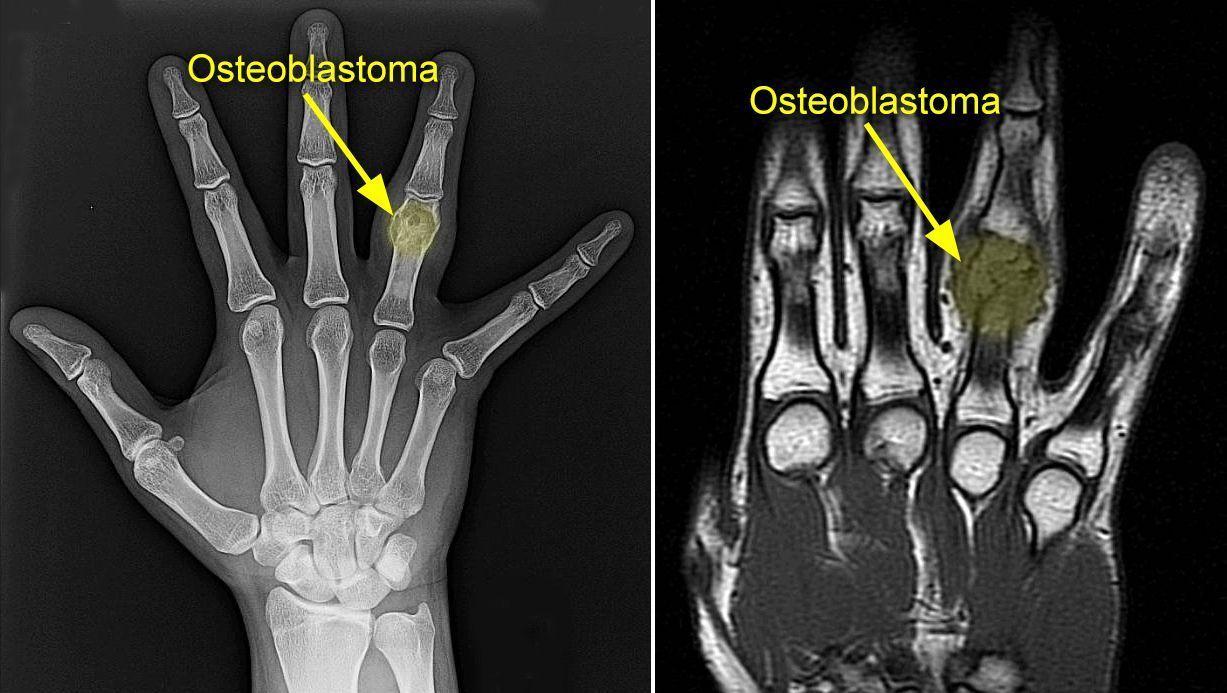

Estos tumores son muy poco frecuentes y suelen aparecer en la columna vertebral pero también en las piernas, las manos y los pies. Según los expertos, la localización más habitual de este tipo de lesiones "se encuentran comúnmente en la cara dorsal de las vértebras y huesos largos".

( Puede aparecer en la columna, manos, piernas y pies. )

Para diagnosticar los osteoblastomas, los especialistas realizan radiografías y otras pruebas de diagnóstico por imagen como tomografía computarizada (TC) y resonancia magnética nuclear (RMN). "Para confirmar el diagnóstico de osteoblastoma, además, se toma una muestra de tejido y lo examina al microscopio (biopsia)", señalaron los expertos.